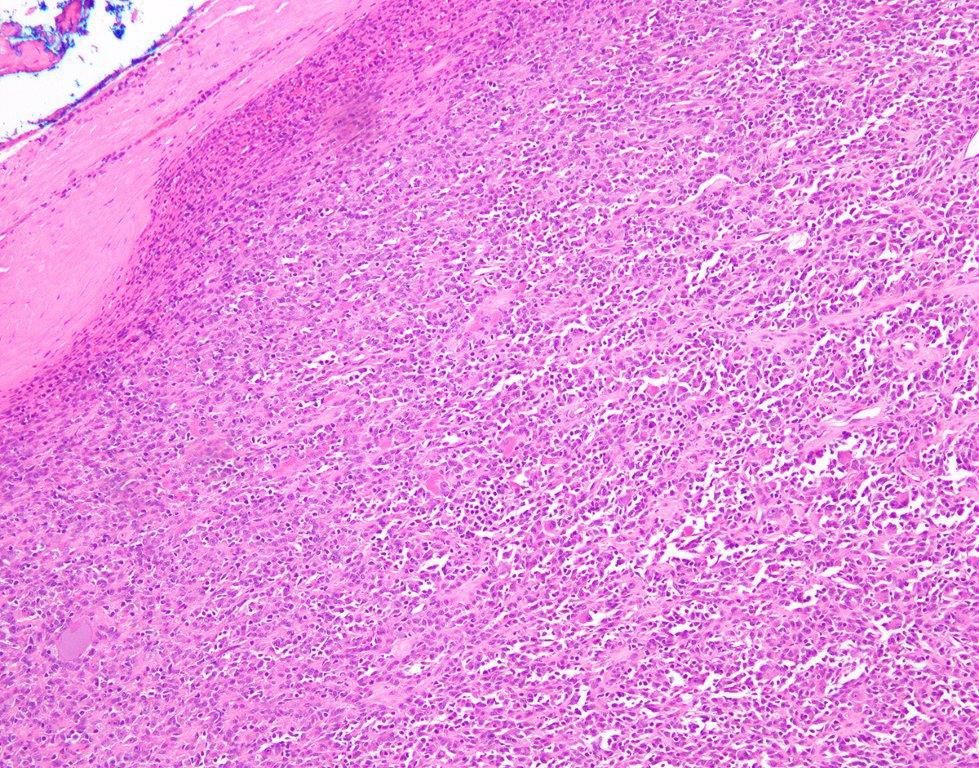

#PathSky Laryngeal mass, older adult male. Primitive, highly vascular round cell neoplasm for the most part.